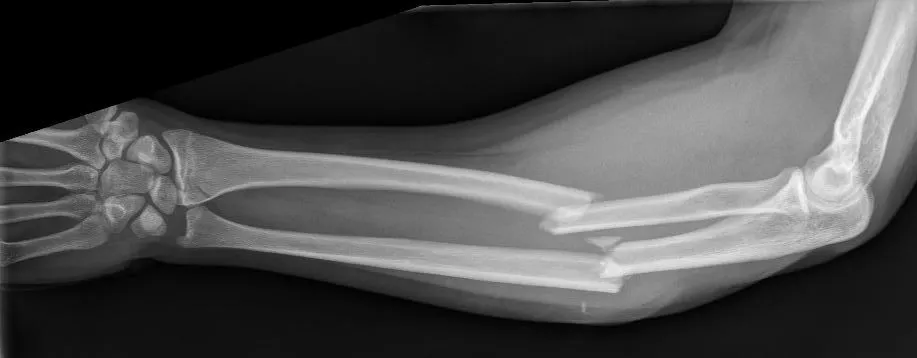

- Technisch onderzoek: Een röntgenfoto van de onderarm wordt gemaakt om de breuk(en) in beeld te brengen. Daarbij neemt men doorgaans de hele onderarm inclusief pols én elleboog op de foto om geen bijkomende letsels te missen. De röntgenbeelden laten zien welk bot (of beide) gebroken is en hoe de breukdelen staan. Soms is aanvullend een CT-scan nodig bij zeer complexe breuken, bijvoorbeeld om de breuklijn richting een gewricht in detail te beoordelen.

Een onderarmfractuur is een botbreuk van één of beide botten in de onderarm. De onderarm bestaat uit twee lange botten: het spaakbeen (radius) aan de duimzijde en de ellepijp (ulna) aan de pinkzijde. Bij een onderarmfractuur kan het spaakbeen gebroken zijn, de ellepijp gebroken zijn of zelfs beide botten tegelijkertijd gebroken zijn. Meestal breken beide botten door een krachtige impact, bijvoorbeeld bij een val van hoogte, een sportongeval of een auto-ongeluk. Onderarmfracturen variëren van eenvoudige breuken (waarbij de botstukken netjes op hun plaats blijven) tot complexe breuken met meerdere fragmenten en mogelijke ontwrichting van nabijgelegen gewrichten.

- Indicatie voor operatie: Veel onderarmfracturen, vooral bij volwassenen, worden operatief behandeld. Als de botdelen verplaatst zijn of als beide botten gebroken zijn, zal men meestal voor een operatie kiezen. Complexe combinaties (zoals een Monteggia- of Galeazzi-letsel) vereisen vrijwel altijd een operatie om de arm weer goed te krijgen. Met andere woorden, zijn uw spaakbeen én ellepijp gebroken en staan de stukken niet goed, dan volgt een operatie om alles correct te zetten.